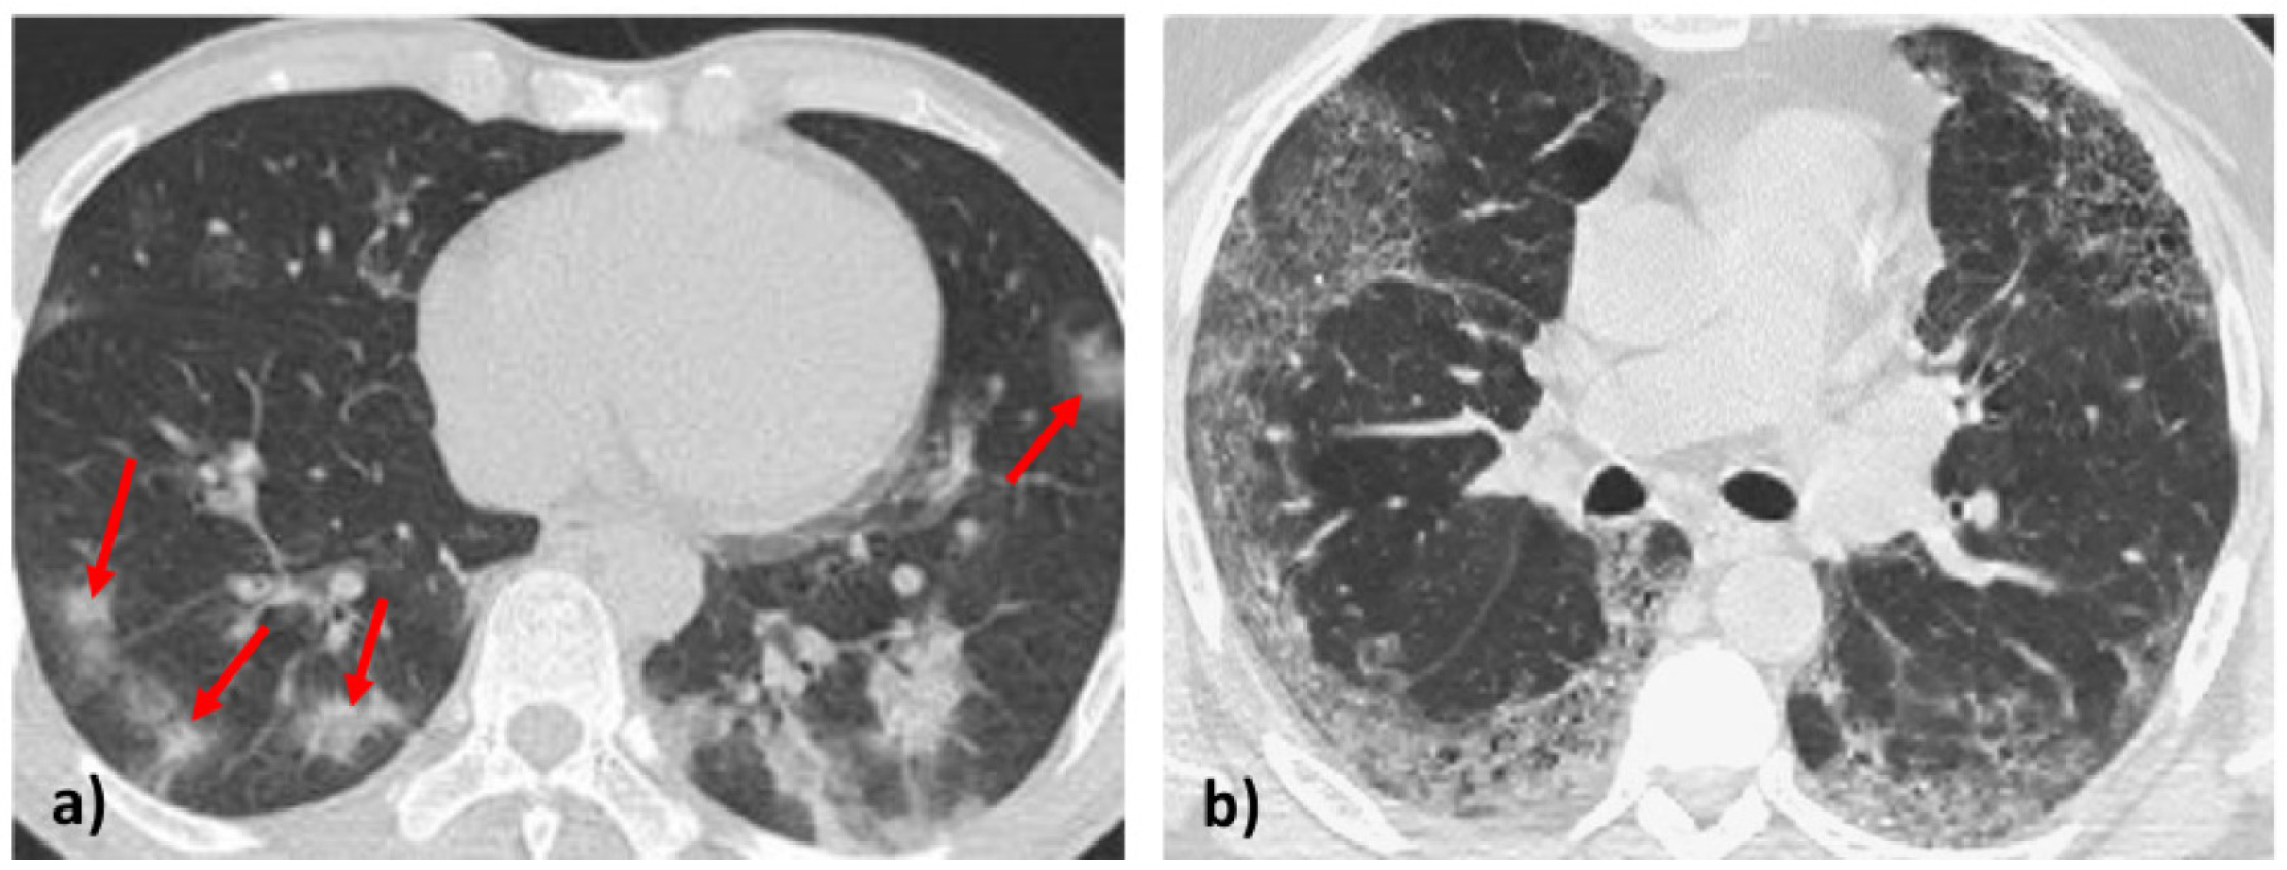

- Parekh, M.; Donuru, A.; Balasubramanya, R.; Kapur, S. Review of the chest CT differential diagnosis of ground-glass opacities in the COVID era. Radiology 2020, 297, E289–E302. [Google Scholar] [CrossRef] [PubMed]